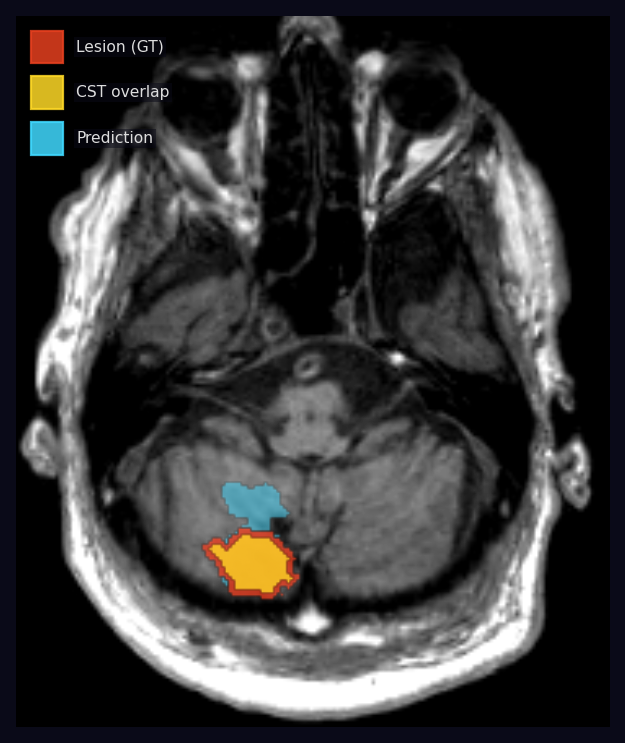

πΊοΈ JHU CST + SMATT Motor Atlas Overlap Features

UOA: 8 loss segmentations Β· Motor features + Clinical features